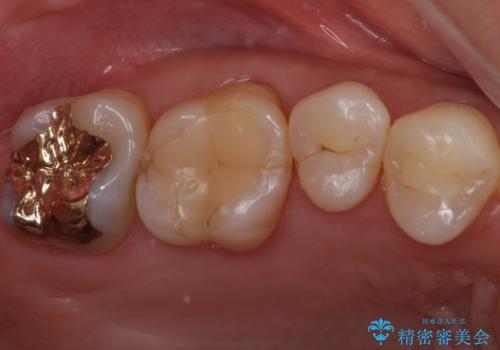

検査で見つかった虫歯 セラミッククラウンでの治療

担当医 岡田康成